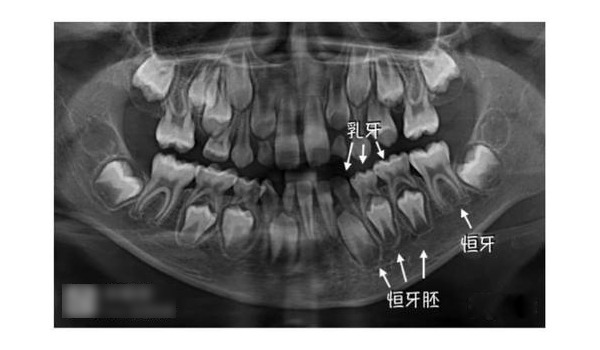

1、乳牙和恒牙_晚什么出齊

家長(zhǎng)不必過(guò)分擔(dān)心寶寶牙齒出得慢。一般要到三歲左右,寶寶的乳牙才會(huì)完全出齊。與此同時(shí),恒牙大部分也正在孕育之中。當(dāng)寶寶步入小學(xué)時(shí),會(huì)長(zhǎng)出第一顆六齡齒。一般等到小學(xué)高年級(jí)后,乳牙會(huì)全部脫落,換上滿(mǎn)口的恒牙。但也有的孩子到了中學(xué)才換好牙齒。